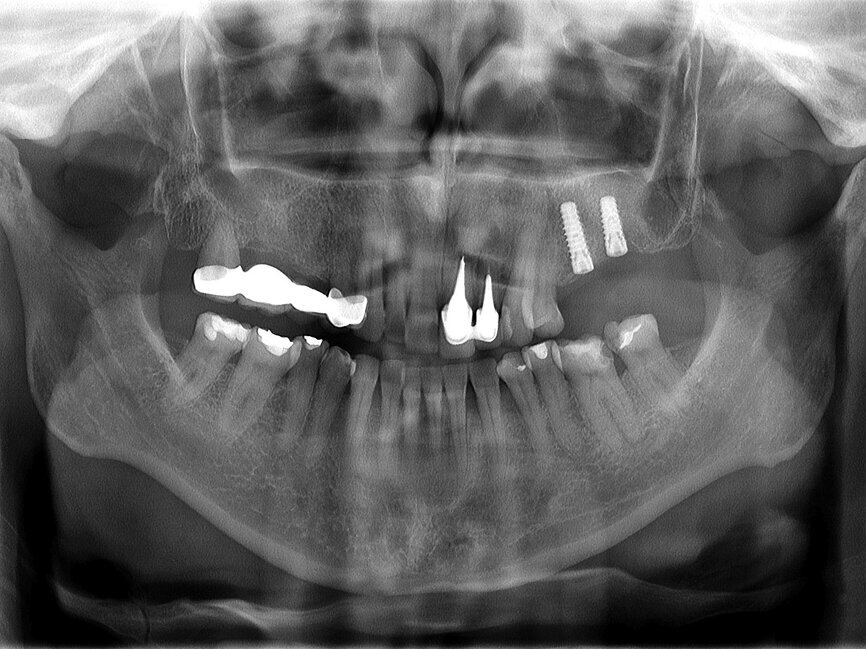

Fig. 11: Panoramic finding after six months of uneventful healing.

After the uneventful integration period of six months, the implants were restored with a splinted, screw-retained metal ceramic restoration (Figs. 11 & 12). This was done to minimise the stress in both the peri-implant bone area and on the implants themselves, all according to the previously discussed biomechanical facts.